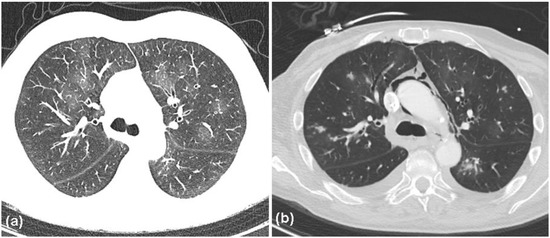

2. Case Report